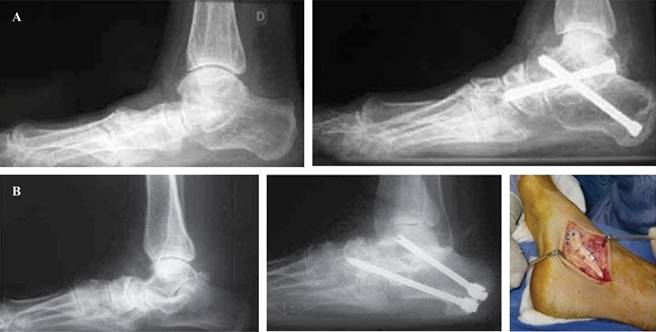

La triple artrodesis a menudo precisa de gestos accesorios como el alargamiento del gastrocnemio medial, en último lugar120),(121 (Figura 10), tenotomía de alargamiento del tendón de Aquiles u osteotomías plantarizantes del primer radio (Cotton) en el caso de una supinación residual del antepié. Con menos frecuencia podemos encontrarnos con la necesidad de realizar otros gestos sobre tendones peroneos o articulaciones distales a astrágalo escafoidea así como reconstrucciones de ligamento deltoideo o procedimientos sobre la articulación tibioastragalina dependiendo de su estado y balance de partes blandas.

Figura 10: Triple artrodesis, A) retropié rígido en valgo, con injerto óseo autólogo. B) Artrosis subastragalina. Inestabilidad medial refuerzo con tendón tibial posterior.